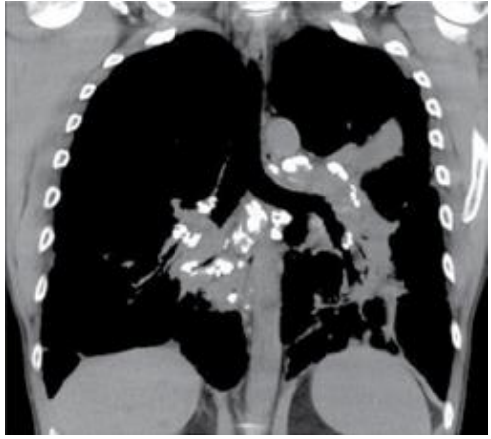

Paciente do sexo feminino, 46 anos, sem histórico de tabagismo, queixando-se de tosse seca e cansaço. A paciente realizou tomografia computadorizada como parte da rotina diagnóstica.

Em relação ao diagnóstico e às características radiológicas da sarcoidose, assinale a afirmativa correta.